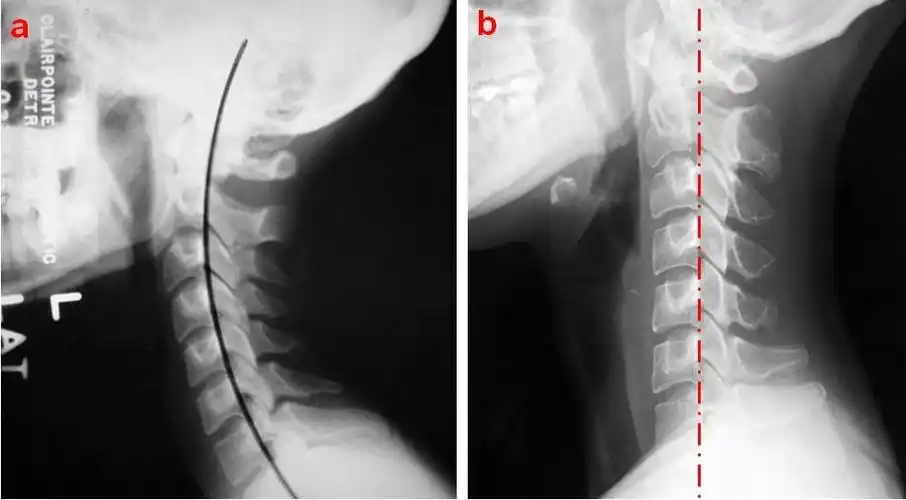

颈椎生理曲度变直怎么办?

颈椎曲度变直是怎么回事儿?曲度变直了该怎么办?

颈椎及椎间盘前缘高度变小等一系列改变, 最终出现颈椎曲度改变 (变直

颈椎生理曲度是指第45颈椎向前凸出的弧度,某些原因引起弧度消失时